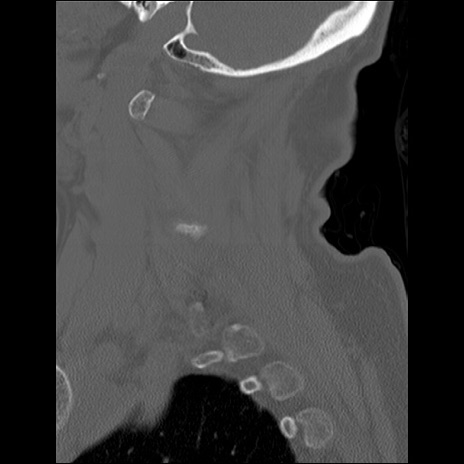

症例48 頚椎CT(矢状断像)

頚椎CT

冠状断像